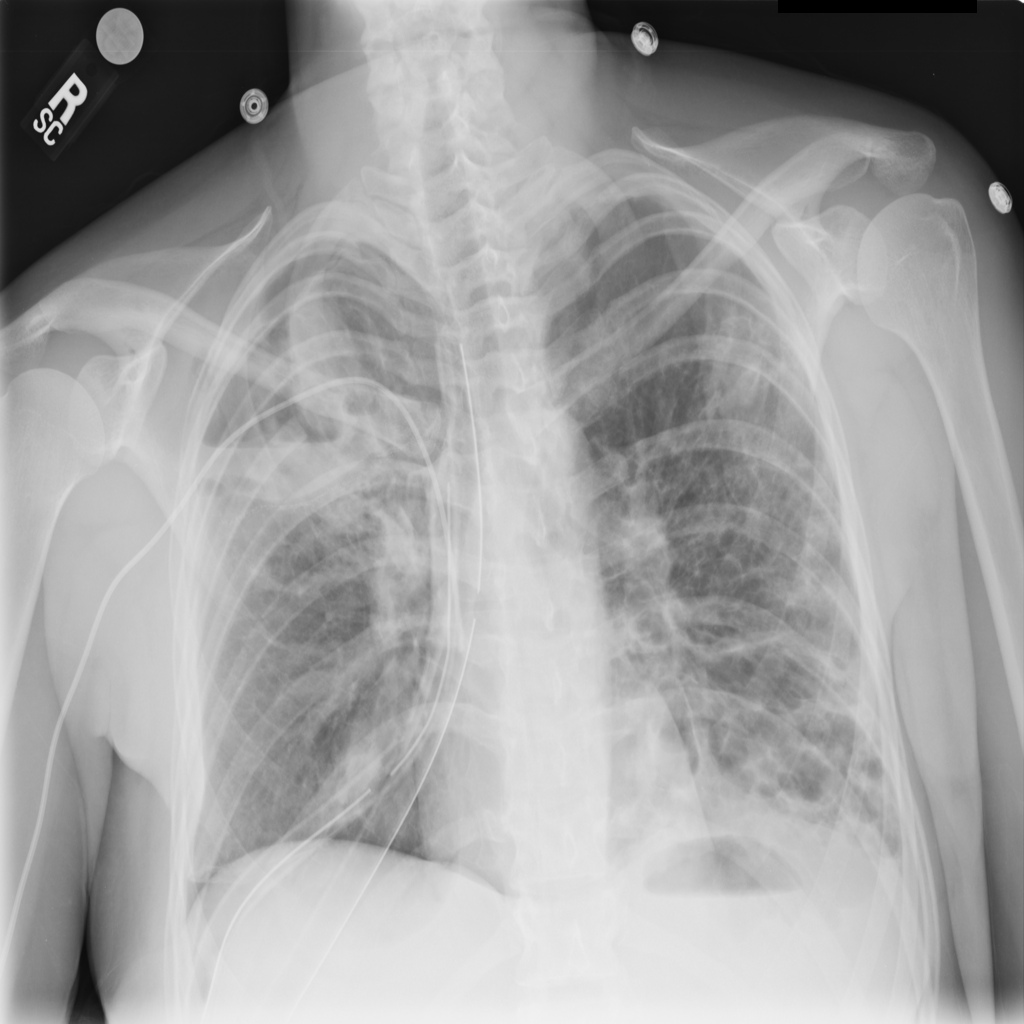

PAT-894B · IMG-000Emphysema

PAT-894B · IMG-000

PA